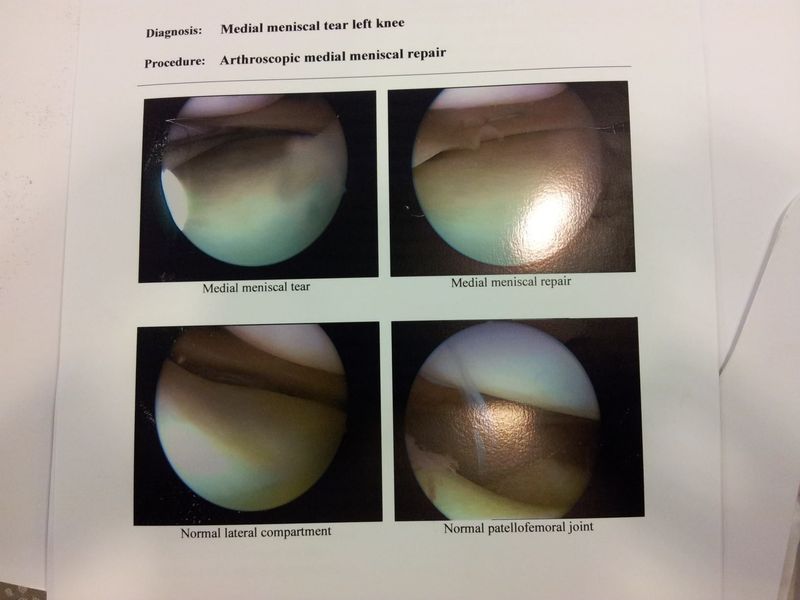

Do have other good news, my left knee got operated on (nearly 3 years after injuring it) on 4th July!

Very large tear of the medial meniscus and the right knee has a 2.5 year old bone bruise in it... so hopefully when the left is healed I can take it easy on the right so that'll heal.

Good updates. Ive had surgery on all 4 of my meniscus' (wrestling)

No fun. Hope the healing goes well!